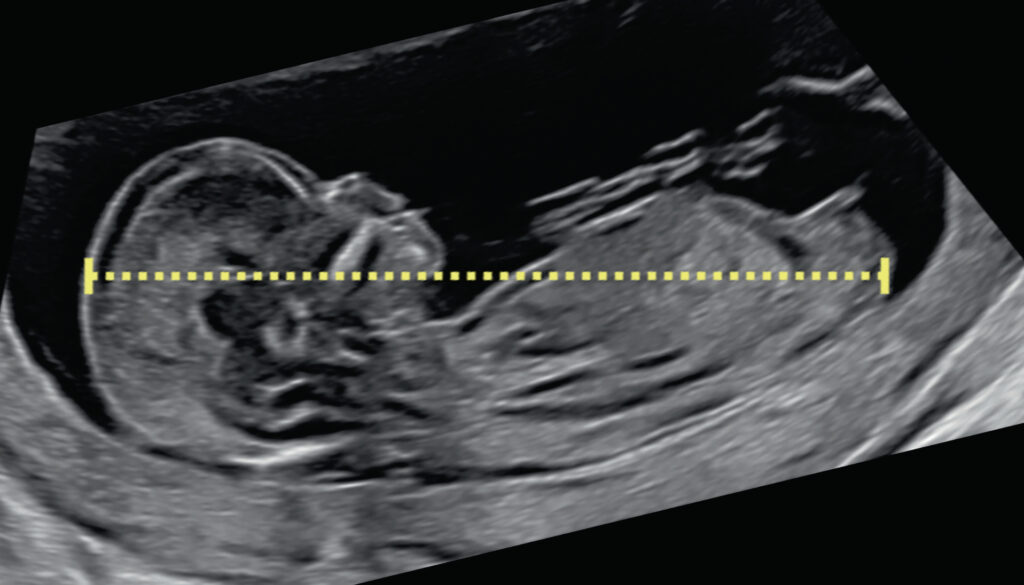

O ultrassom morfológico do 1º trimestre é um exame de imagem realizado entre a 11ª e a 14ª semana de gestação.

Ele permite avaliar a anatomia inicial do bebê, identificar possíveis malformações e verificar se o desenvolvimento está de acordo com a idade gestacional.

Além disso, esse exame fornece dados importantes sobre a saúde materna e fetal, como a medida da transluscência nucal, que auxilia na triagem de síndromes cromossômicas.

Além da importância diagnóstica, o exame tem um grande valor emocional. É, muitas vezes, o primeiro momento em que os pais conseguem ver imagens mais nítidas do bebê, fortalecendo o vínculo afetivo já nas primeiras semanas da gestação.